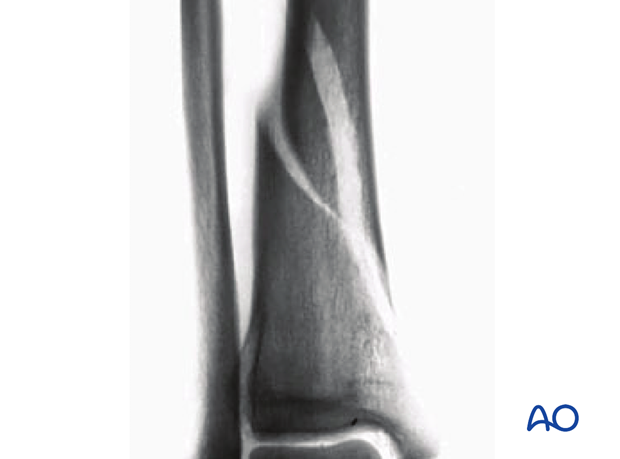

This AP radiograph indicates a long spiral fracture involving the distal metadiaphysis, without intraarticular extension.